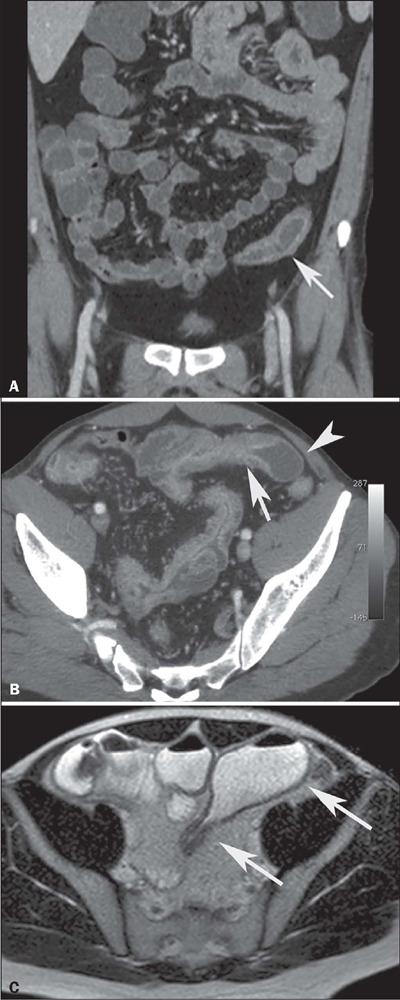

Crohn's disease is an inflammatory bowel disease that can affect any segment of the gastrointestinal tract. It has a variable clinical course, with alternating periods of disease activity and remission. Because the incidence and prevalence of Crohn's disease have been increasing, evaluation by imaging methods has become more important. The most widely used methods are computed tomography enterography, magnetic resonance enterography (as an elective examination), and contrast-enhanced computed tomography (in the context of emergency). Computed tomography enterography and magnetic resonance enterography are useful for diagnosis, follow-up, evaluation of complications, and prognosis. Both can be used in order to evaluate the small bowel loops and the associated mesenteric findings, as well as to evaluate other abdominal organs. They both also can detect signs of disease activity, fibrosis, penetrating disease, and complications. The interpretation of such changes is essential to the multidisciplinary approach, as is the standardization of the nomenclature employed in the reports. In this paper, we review and illustrate the imaging findings of Crohn's disease, using the standardized nomenclature proposed in the multidisciplinary consensus statement issued by the Society of Abdominal Radiology, the Society of Pediatric Radiology, and the American Gastroenterology Association, with recommendations for descriptions, interpretations, and impressions related to those findings.

克罗恩病是一种炎症性肠病,可累及胃肠道的任何节段。其临床病程多变,疾病活动期和缓解期交替出现。由于克罗恩病的发病率和患病率一直在上升,通过影像学方法进行评估变得更加重要。最常用的方法是计算机断层扫描小肠造影、磁共振小肠造影(作为选择性检查)和增强计算机断层扫描(在急诊情况下)。计算机断层扫描小肠造影和磁共振小肠造影对诊断、随访、并发症评估及预后判断均有帮助。两者均可用于评估小肠肠袢及相关肠系膜表现,以及评估其他腹部器官。它们还都能检测疾病活动、纤维化、穿透性病变及并发症的征象。对这些改变的解读对于多学科诊疗方法至关重要,报告中使用的命名标准化也同样重要。在本文中,我们使用腹部放射学会、儿科放射学会和美国胃肠病学会发布的多学科共识声明中提出的标准化命名,回顾并阐述克罗恩病的影像学表现,并对与这些表现相关的描述、解读及印象给出建议。